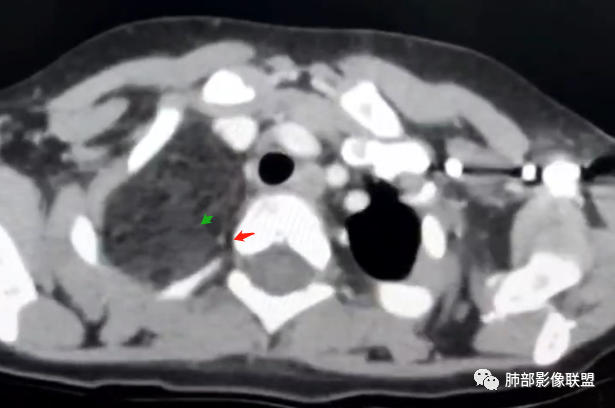

右上纵隔混杂密度肿块,边缘光整,与纵隔分界清,其内多发脂肪密度,增强无明显强化,其内血管穿行,考虑纵隔脂肪母细胞瘤,鉴别畸胎瘤,脂肪肉瘤。

患儿3岁 咳嗽检查发现纵隔占位。右肺上叶受压表现,占位以脂肪组织密度为主,似见分隔,首先考虑为脂肪母细胞瘤,鉴别脂肪瘤,畸胎瘤。

病灶属于交界区,主体位于肺内,占位效应明显,前方突入胸壁,胸腺受压变形,胸膜显示欠清楚;病灶包绕上叶肺动脉;似乎有体动脉供血。符合肺内的点:包绕上叶肺动脉分支;符合纵隔的点:前方似乎突入胸壁,与胸腺关系比较密切,但是与上腔静脉的关系提示病灶不支持纵隔来源,前纵隔的常规会将上腔静脉受压后移、外移,这是不符合的。

从这个角度符合肺内的,有一点不太踏实的是:似乎突入前胸壁。

手术记录:见右肺上叶肿物,肿物与右肺上叶关系密切。与纵隔无粘连,逐步分离肿物,见肿物大小约6cm*5cm,边界清楚,于右肺上叶粘连,边界清楚,肿物包绕右肺上叶血管及支气管。超声刀逐步游离肿物,完整切除肿物,右肺上叶肺组织无破溃,表面无出血。

2.肺动脉穿行也许是肺内来源最重要支持点!